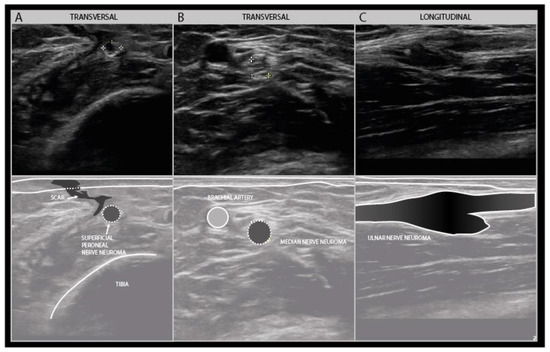

7. Neuroma Outgrowth and Remodeling during Recovery

Depending on the extent of the connective tissue trauma, nerve recovery will give rise to changes in the shape and size of the nerve under study. A traumatic neuroma represents a disordered, hyperplastic growth response to nerve injury, that can give an increase in nerve size from 125 to 1600% of its normal size in the first 1–2 months following the injury [45] (Figure 14).

Figure 14.

Examples of traumatic neuroma in continuity. Transverse view of a small superficial peroneal nerve neuroma following a motorbike injury (A). Transverse view of a median nerve traction neuroma from a distal elbow injury (B). Longitudinal view of a large disorganized ulnar neuroma from grenade shard injury to the forerarm (C).

In case of a nerve injury of Sunderland grade 3 or 4, the disruption of the endoneurium and next the perineurium will lead to the formation of intraneural fibrosis during recovery. This intrafascicular fibrosis can delay, divert or block axonal outgrowth, and in addition lead to the constriction of nerve segment by scar tissue [46]. These mechanisms lead to a disorderly growth of axons that result in a fusiform swelling of the injury site. Many of these axons will not reach their original target tissue (i.e., misrouting), and some will be unable to reinnervate any muscle or skin at all. In the case of full nerve transection, or Sunderland grade 5 lesion, the severed nerve ends will retract over the length of a few centimeters because of the epineurium’s elastic properties. The stumps will also form neuromas, while the distal nerve segment fasciculi will undergo a contraction of the endoneurial tubes after Wallerian degeneration has occurred, so that the cross-sectional fascicular area can be reduced up to around 60% after 3 months [46]. No direct relation seems to be present between the neuroma size and nerve function or recovery, although patients with very large neuromas of more than 5x the normal nerve size usually have no function left in the affected nerve and do not improve [45]. In patients that show clinical recovery over a period of 3–9 months, the neuroma will usually undergo remodeling and decrease in size, but possibly not all the way back to its healthy state. This slight residual enlargement following (any type of) nerve pathology, e.g., also inflammatory or ischemic lesion besides trauma, has been dubbed a "damage pattern" by some.